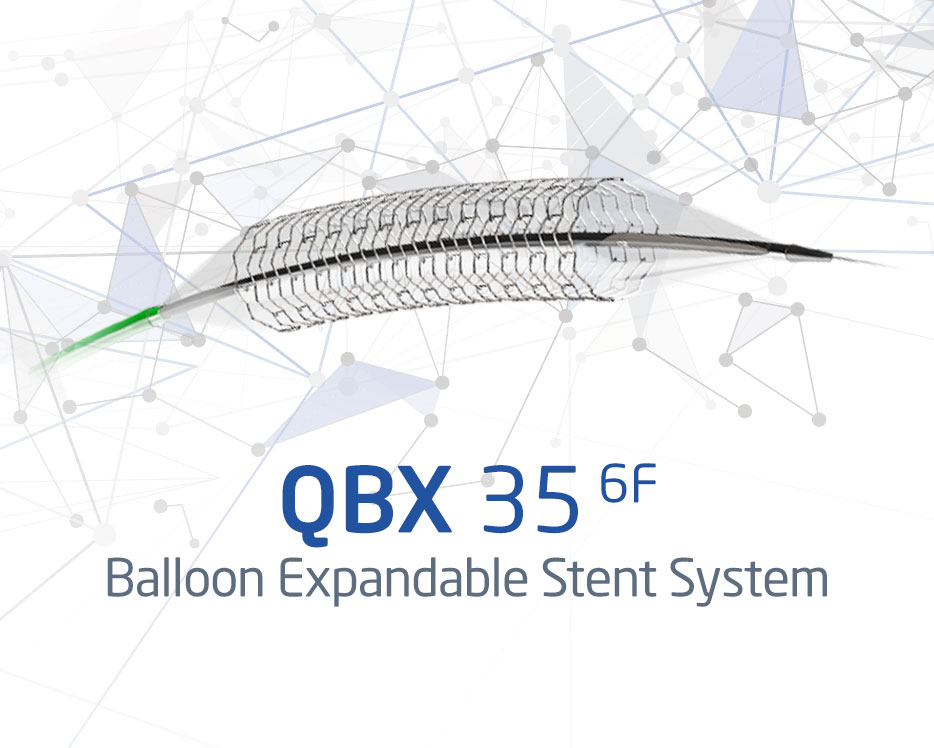

QBX 35 6F

Balloon Expandable Stent System

See Product